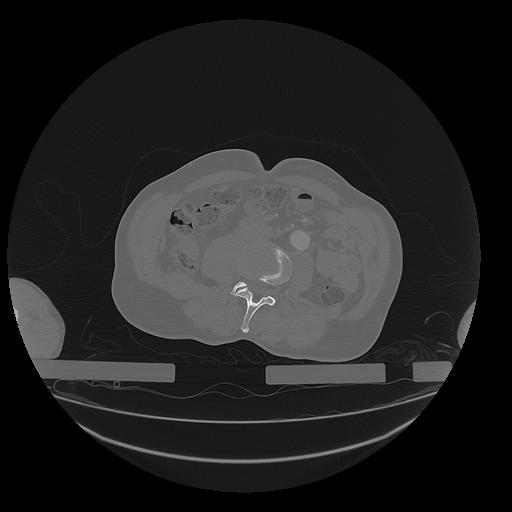

31 PULMON,CE,Vol,1.0,PULMON,,